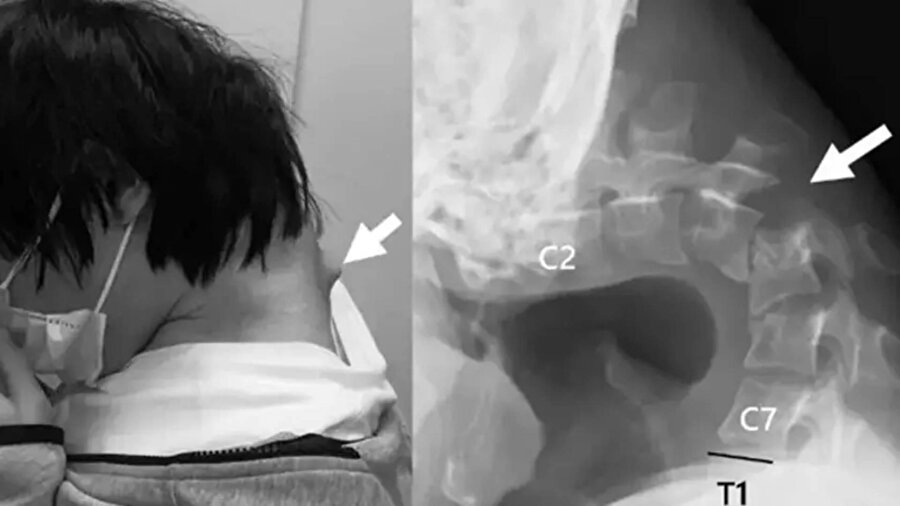

Japonya'da 25 yaşındaki bir genç, akıllı telefonuna çok fazla bakması nedeniyle "düşük baş sendromu" geliştirdi, yani bir başka deyişle boynu yamuldu.

ScienceDirect'in haberine göre, boynunu uzun süre öne eğerek telefon kullanan genç, zamanla başını kaldıramaz hale geldi.

Genç, tedaviye başvurmadan önce şiddetli boyun ağrısı ve yutma zorluğu yaşamaya başladı ve bu da hızla kilo vermesine neden oldu. Daha sonra boynunun arkasında başını destekleyemeyecek kadar güçsüz hale getiren büyük bir yumru oluştu.

Bir MRI taraması, başının uzun süre doğal olmayan bir pozisyonda olmasının yıkıcı etkilerini gösterdi. Servikal omurgası hasarlıydı, pozisyonu bozuktu ve aşırı gerilmeden dolayı yara dokusu vardı. Omurgasında ciddi hasar ve deformasyon tespit edilirken, boyun kaslarının işlevini yitirdiği belirlendi.

25 yaşındaki adama, sürekli telefonuna bakması nedeniyle başını kaldıramamaya başlaması üzerine Düşük Kafa Sendromu teşhisi konuldu.

Operasyonda hasarlı omurlar ve dokular çıkarılıp, boynu hizalamak için vida ve metal çubuklar yerleştirildi. Ameliyattan altı ay sonra hasta başını kaldırmaya başladı, bir yıl içinde ise hareket kabiliyeti ve duruşunda belirgin iyileşme gözlendi. Doktorlar, genç yaşta ortaya çıkan bu vakanın nadir olduğunu belirtirken, “Düşük Kafa Sendromu”nun akıllı telefon ve tablet kullanımına bağlı olduğunu vurguladı.